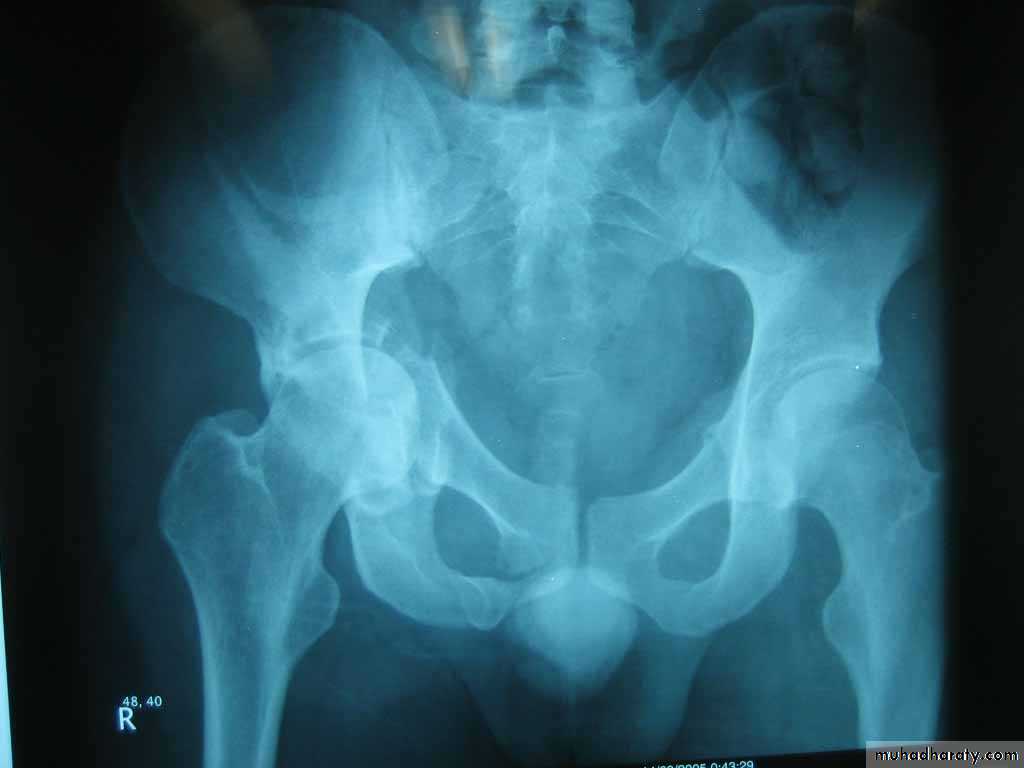

Anterior dislocation of the hip

it is rare .Clinically : the leg is externally rotated , abducted and slightly flexed , not short .

sometimes the leg is abducted to right angle .

X-ray : AP view , the dislocation is obvious , any doubt is resolved by lateral view .